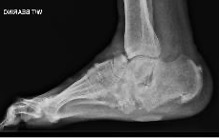

Differential diagnoses include cellulitis, deep infection, DVT, and gout; appropriate investigations may be considered to rule out these pathologies. Plain radiographs may initially appear normal but show bone fractures and joint dislocations in late presentations. MRI is extremely useful in the diagnosis of early acute Charcot (but can be difficult to differentiate from infection).

Based on plain radiographs, CN is classified using the Eichenholtz classification as follows:

- Stage 1: destruction / fragmentation

- Stage 2: coalescence

- Stage 3: consolidation

Stage 0 was recently added in which x-rays are normal, but MRI shows evidence of bone oedema and subchondral fractures.